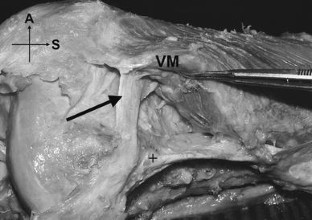

Most descriptions of the extensor mechanism of the knee do not take into account its complexity and variability. The quadriceps femoris insertion into the patella is said to be through a common tendon with a three-layered arrangement: rectus femoris (RF) most superficially, vastus medialis (VM) and lateralis (VL) in the intermediate layer, and vastus intermedius (VI) most deeply. We dissected 20 limbs from 17 cadavers to provide a more detailed description of the anterior components of the knee: the tendon, the patellar retinacula, and the patellofemoral ligaments. Only three of the 20 specimens exhibited the typically described quadriceps pattern. The remainder had bilaminar and even more complex trilaminar and tetralaminar fiber arrangements. We found an oblique head of the vastus lateralis (VLO), separated from the longitudinal head by a layer of fat or fascia, in 60% of the specimens. However, we found no distinct oblique head of the vastus medialis (VMO) in any specimen. The medial patellofemoral ligament (MPFL) was more common than the lateral (LPFL), supporting its suggested role as the principal passive medial stabilizer of the patella. Because the quadriceps muscle group plays a direct role in patellofemoral joint function, investigation into the clinical applications of its highly variable anatomy may be worthwhile with respect to joint dysfunction and failures of TKAs.

Fig. 3